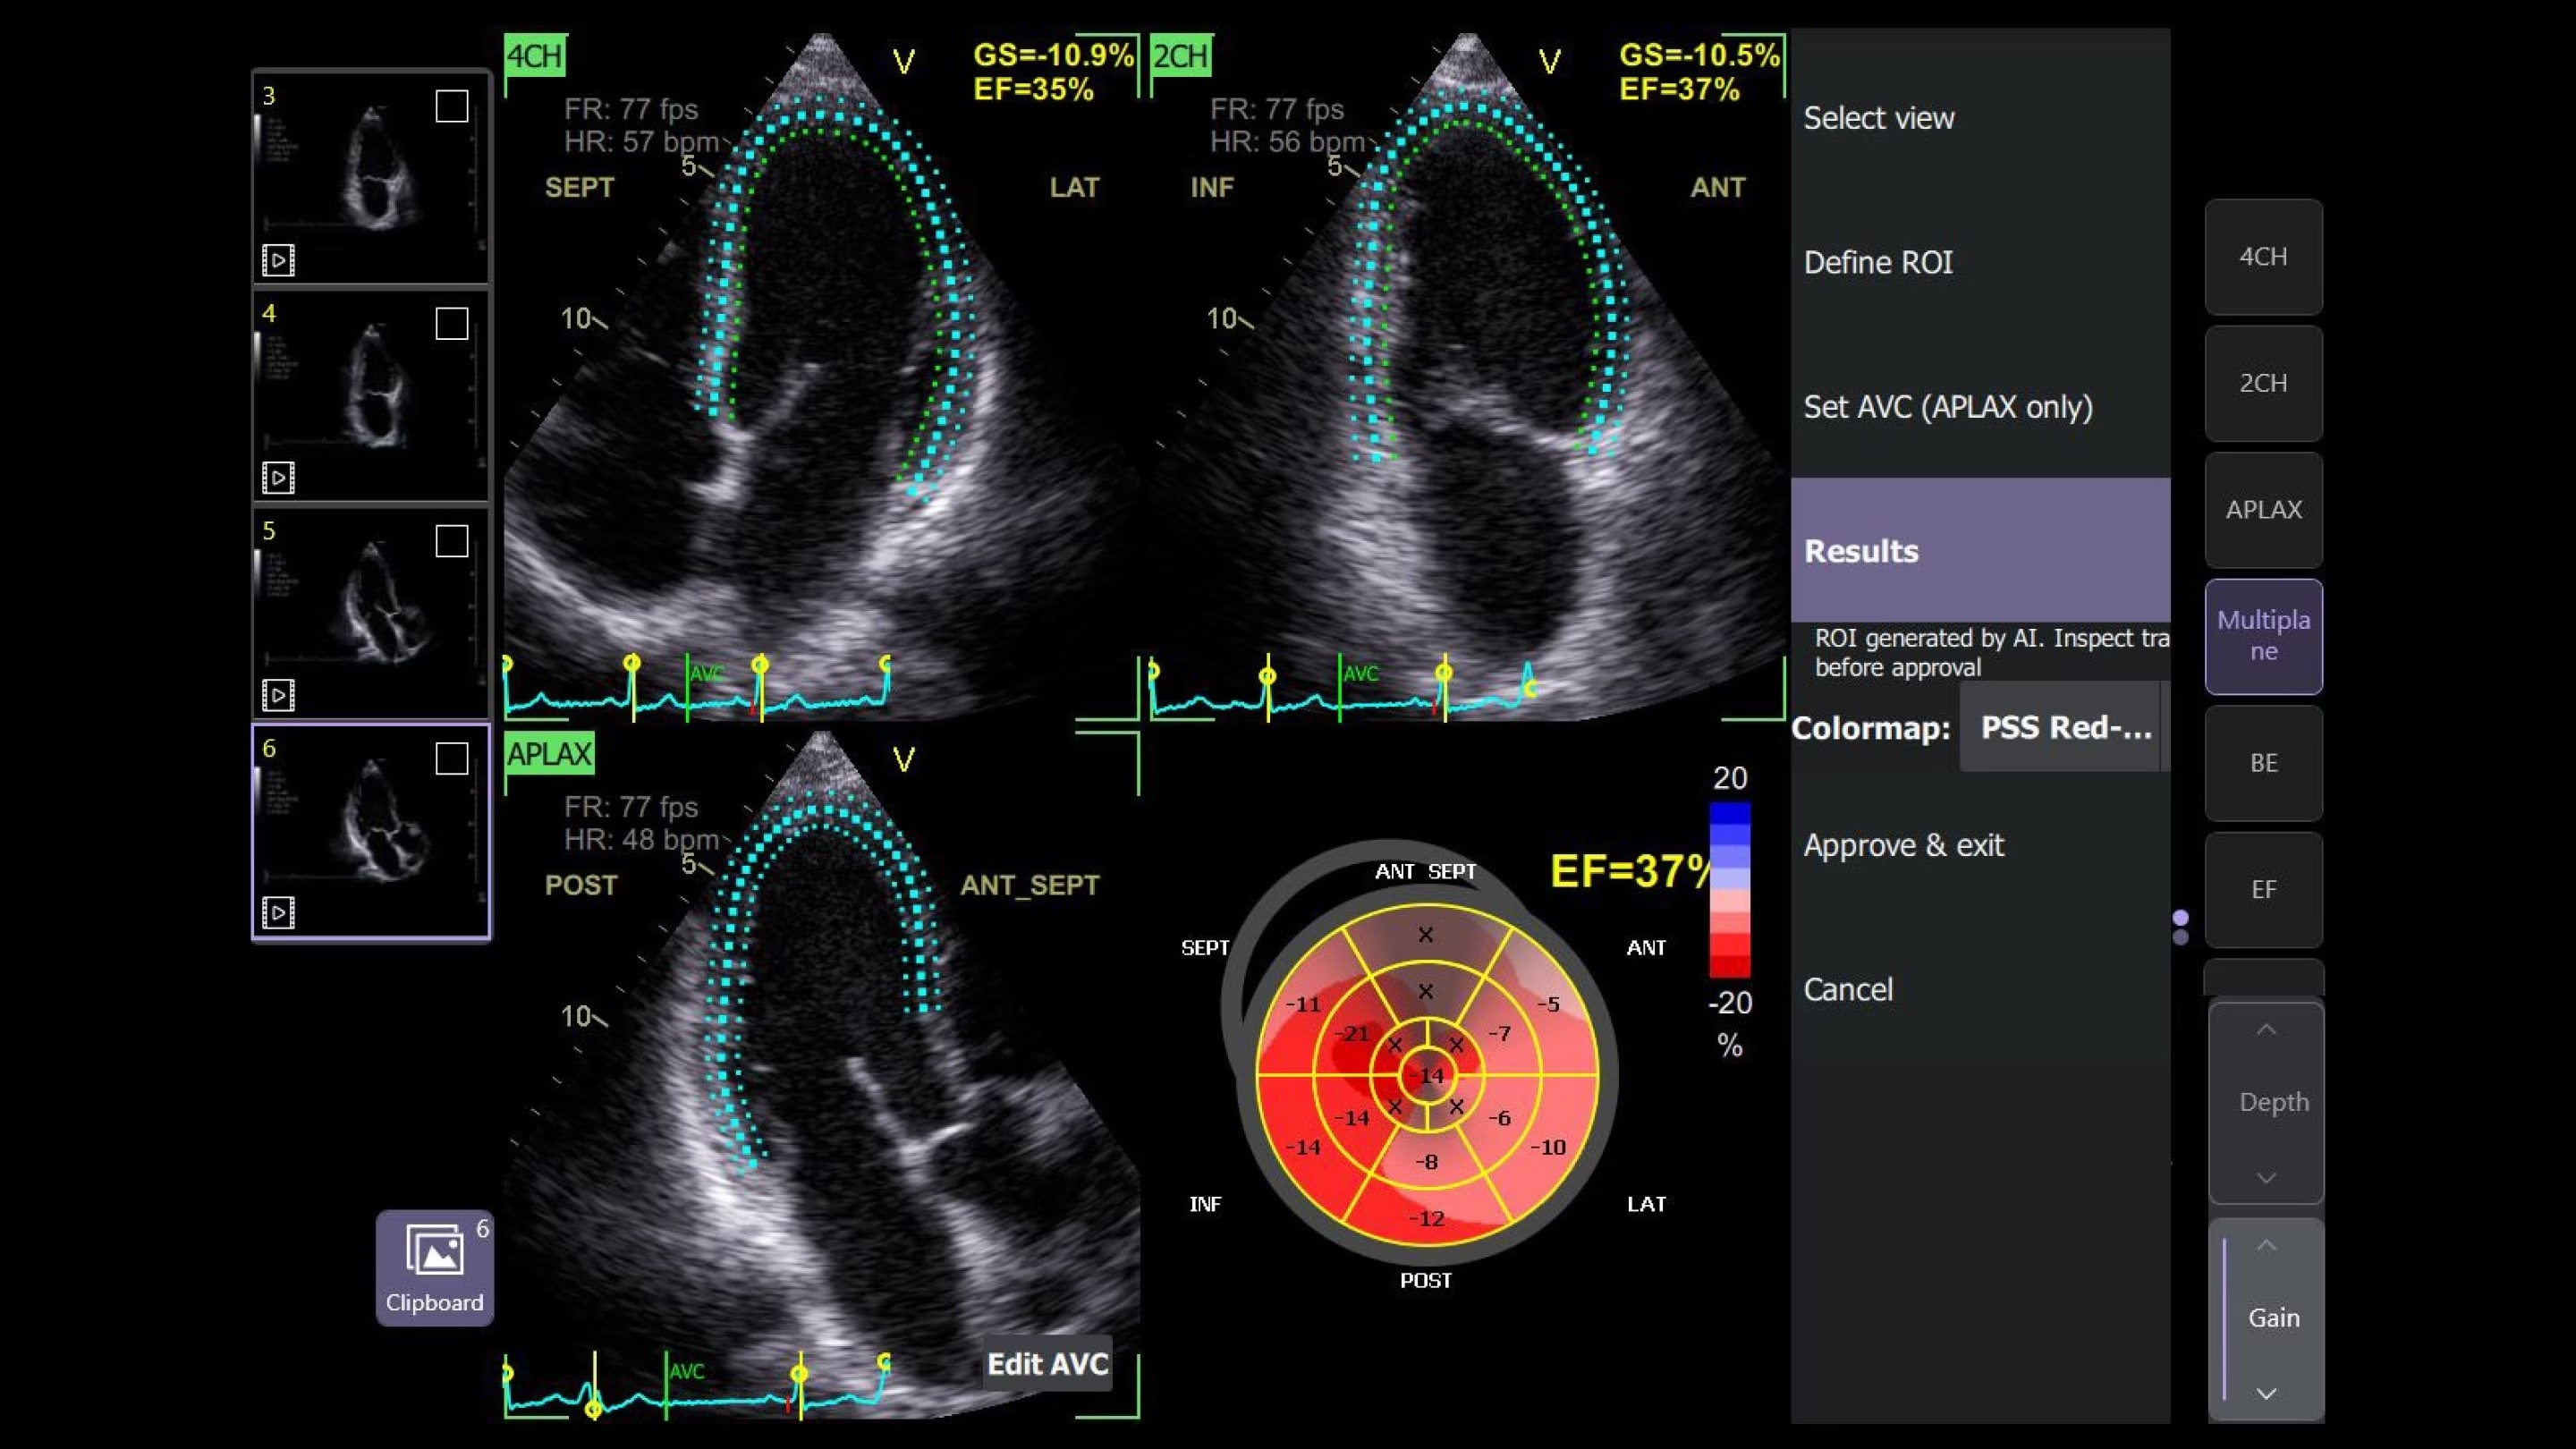

Real-Time EF

For accurate, instant, and rapidly updating results

Capture precise results instantly without requiring ECGs—thanks to Real-Time EF, an AI tool that continuously calculates real-time ejection fraction during live scanning in apical 4CH view. And for improved accuracy, its integrated quality indicator helps users select an optimal view for generating exacting results. Reducing the time it takes to reach a result while helping provide consistency, a study found that Real-Time EF results are within ±10 points of experts in 86% of cases.2